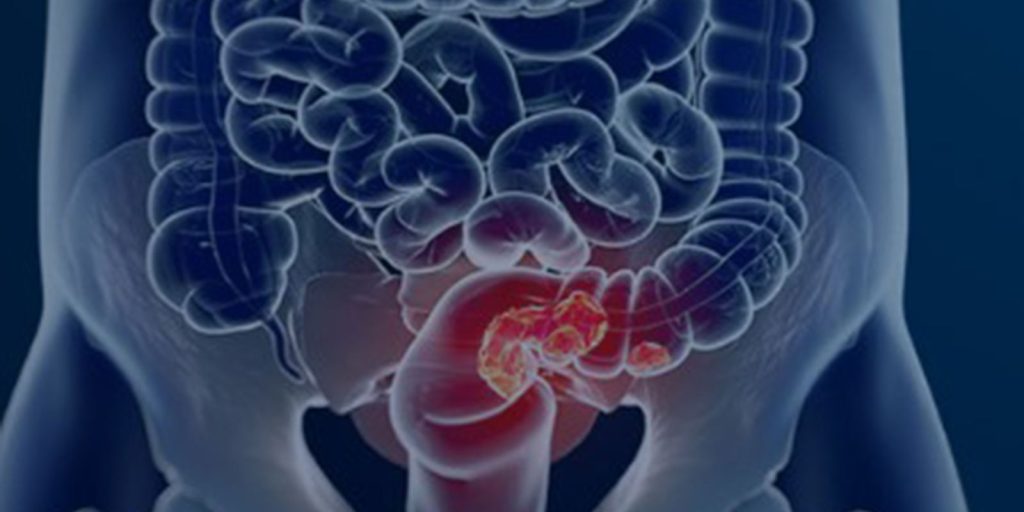

O Sistema Único de Saúde pode ganhar um novo programa para o rastreamento do câncer colorretal, que atinge o intestino grosso e o reto e vem crescendo em número de casos e óbitos.